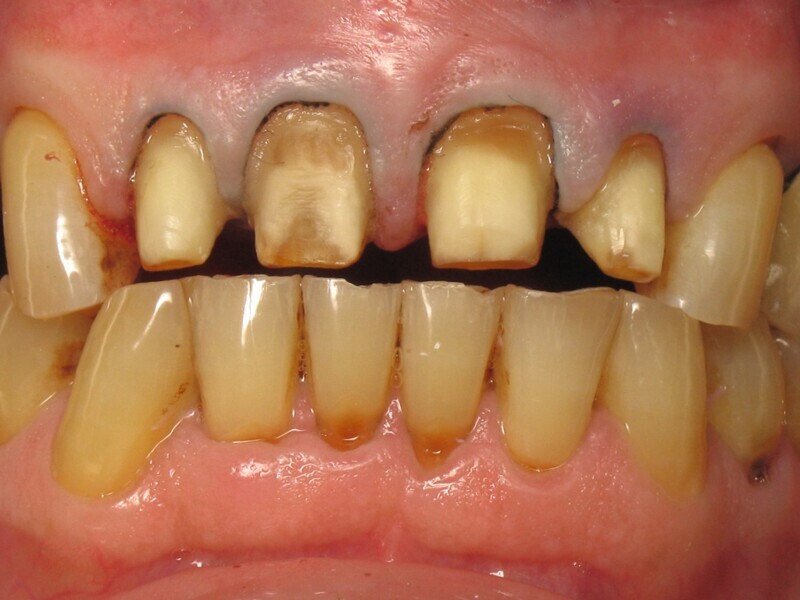

Dans le même temps, les figures 11 et 12 montrent la situation initiale de ce patient, venu en consultation pour la réhabilitation de ses incisives maxillaires. Le diagnostic a révélé un bruxisme nocturne à l’origine de plusieurs destructions coronaires : usure du bord libre, ab fraction, restaurations absentes, fêlures, et une fracture coronaire complexe. Il est aisé de comprendre pourquoi précédemment, le choix du matériau a été porte sur le zircone. Il est également facile de comprendre les motivations de ce patienta retrouver son sourire perdu. Cette dégradation par le temps est inéluctable, mais chez ce patient elle a été particulièrement rapide et agressive. Inverser le cours du temps est donc une évidence pour restaurer la santé dentaire de ce patient.

Fig. 11 : Situation initiale.

Fig. 12 : Vue rapprochée de la situation initiale